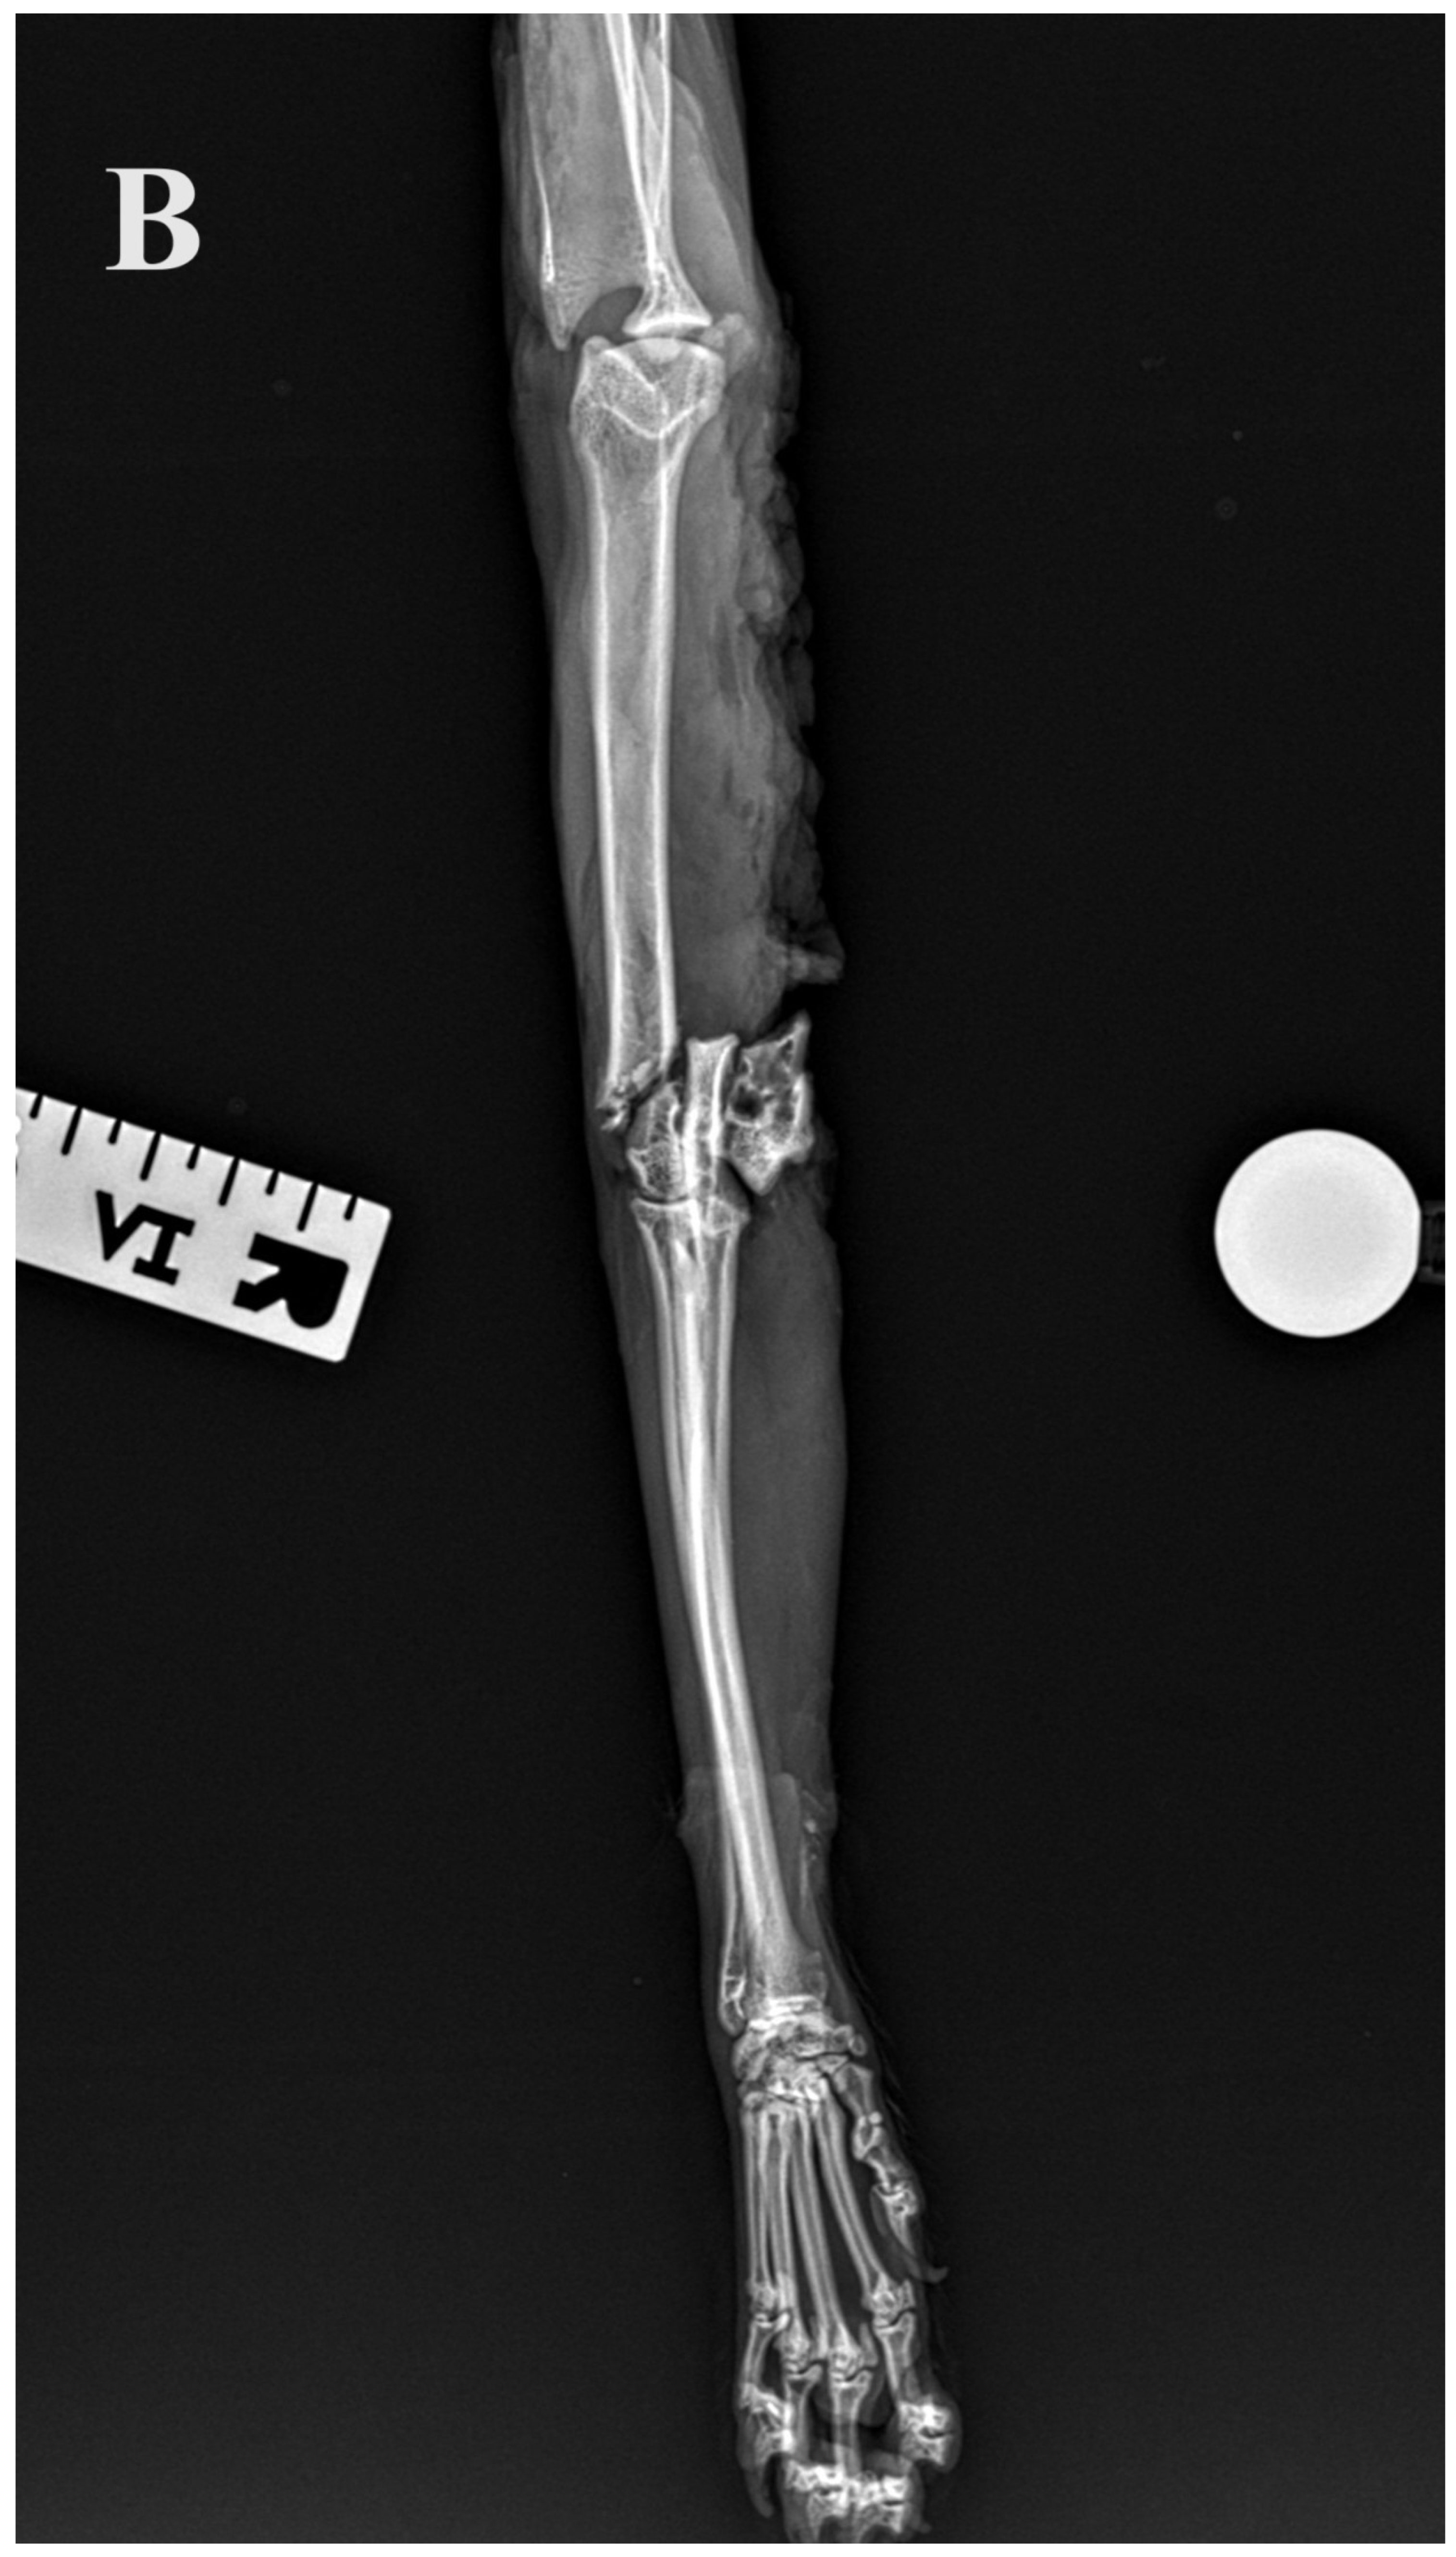

2.3. Radiographic Assessment

Standard calibrated orthogonal radiographs of the amputated limbs were assessed before and after the Y-T fracture creation. For each limb, the length of the humerus, the diameter of the isthmus of the humeral condyle measured on the cranio–caudal radiographs and the fracture configuration were assessed. The implants and repair were assessed on postoperative radiographs. The accuracy of articular surface reduction and the resulting articular surface defect were measured and graded as small (<1 mm), moderate (1–2 mm) or large (>2 mm). In addition, alignment (axial and rotational alignment of the joints above and below the fracture), adjacency (adequate attachment of the main fracture fragments to the comminution zone) and apparatus (implants’ location, placement, security and size) were assessed.

Figure 5.

(A,B) Initial lateral and cranio–caudal radiographs of the right forelimb of a female domestic cat show a displaced Y-T fracture. (C,D) Postoperative lateral and cranio–caudal radiographs show a small articular surface defect (<1 mm) of humeral condyle and adequate alignment, adjacency and apparatus (2.0/2.4/2.7 3D printed plate, 2.4/2.7 straight interlocking bone plate and screws).